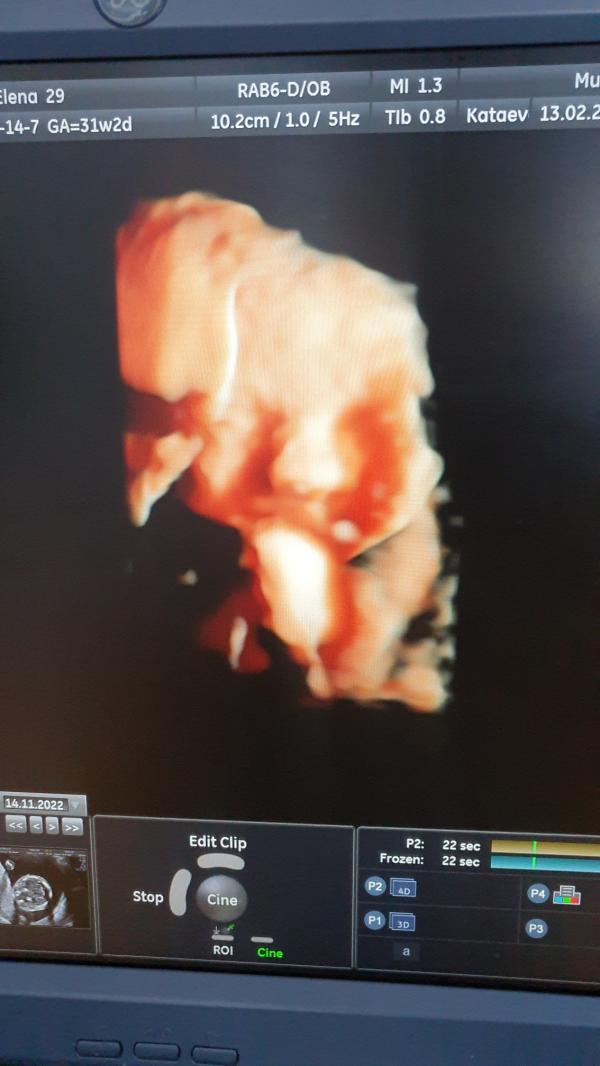

post image

Добрый вечер ! У кого малыши сколько весят на 3м скрининге? 31-32 недели

Мы сегодня 1600 гр,мне кажется старшие дети весили больше 😁